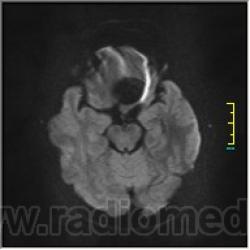

DWI:

частично функционирующая аневризма

Иначе говоря, аневризма с хронической геморрагией, т.к. мы видим фракции крови различного возраста.

Постепенное пристеночное образование тромбов приводит к появлению типичного для аневризмы феномена -слоистости МР сигнала в полости аневризмы. Данная картина демонстрирует слоистый характер тромботических масс в полости аневризмы .Функционрирующая часть имеет низкий сигнал во всех режимах сканирования. Дополнительно-перифокальный отек.

А может более корректно интерпретировать как частично тромбированная аневризма... Уж коь речь идет о фракциях, ну то есть о тромбе по сути.... Ну и плюс перфокальный отек головного мозга (вероятнее цитотоксический+вазогенный).